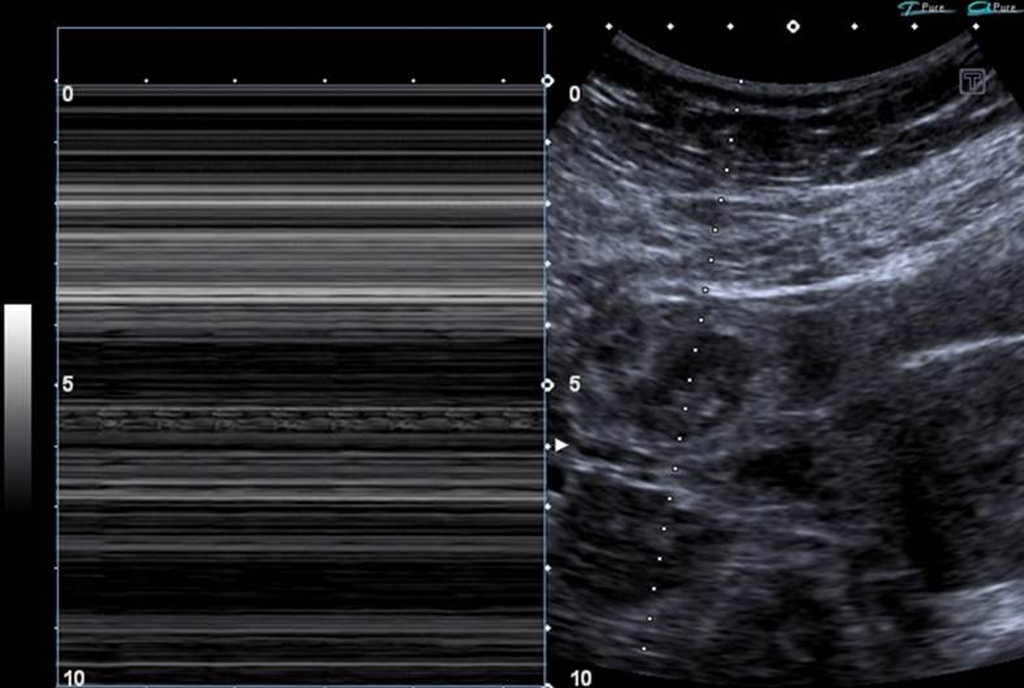

El signo del anillo tubario (tubal ring sign), descrito por primera vez por Timor-Tritsch y Rottem en el a??o 1987, corresponde a un hallazgo ecogr??fico observable en casos de embarazo ect??pico de localizaci??n tubaria1. Se define como una formaci??n anular hiperecog??nica (reacci??n trofobl??stica) que rodea al saco gestacional implantado fuera de la cavidad uterina (fig. 1). Su importancia radica en la alta especificidad y valor predictivo positivo para el diagn??stico de embarazo ect??pico tubario2.

El signo del anillo tubario tiene una frecuencia del 40-68%, siendo la segunda forma de presentaci??n ecogr??fica del embarazo ect??pico, luego de la presencia de una masa anexial2.

Las diferentes caracter??sticas ultrasonogr??ficas permiten clasificar a la entidad en tres categor??as de acuerdo con el tipo de contenido embrionario o extraembrionario4.

Tipo II: trompa de Falopio dilatada que presenta frecuentemente un anillo tubario delgado con centro hipoecog??nico o ligeramente hiperecog??nico, pero sin saco gestacional o estructura embrionaria en su interior.

Tipo III: la trompa de Falopio no logra demostrarse, aunque se reconoce l??quido libre en el fondo de saco de Douglas, ausencia de estructuras embrionarias o extraembrionarias intrauterinas y subunidad beta de gonadotrofina cori??nica humana (hCG) s??rica positiva.